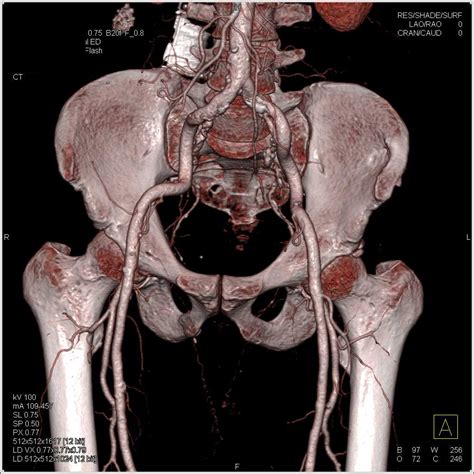

Diagnosing hip joint effusion typically involves a combination of physical examination, medical history, and diagnostic tests. The diagnostic process may include:

• Imaging Tests: X-rays, MRI, or ultrasound to visualize the hip joint and detect fluid accumulation.